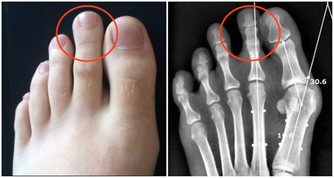

3、手腳發麻、腫脹

如果長期感覺腿部麻木、有腫脹感,也並非是其他疾病所引起的,那麼或是血栓流入動脈所致。

當血栓形成堵塞血管之後,這一部分的肌肉就會出現缺血,皮膚也會變得蒼白,體溫下降,摸起來冰涼冰涼的。時間久了,腿部容易出現腫脹,嚴重的還會伴有疼痛。